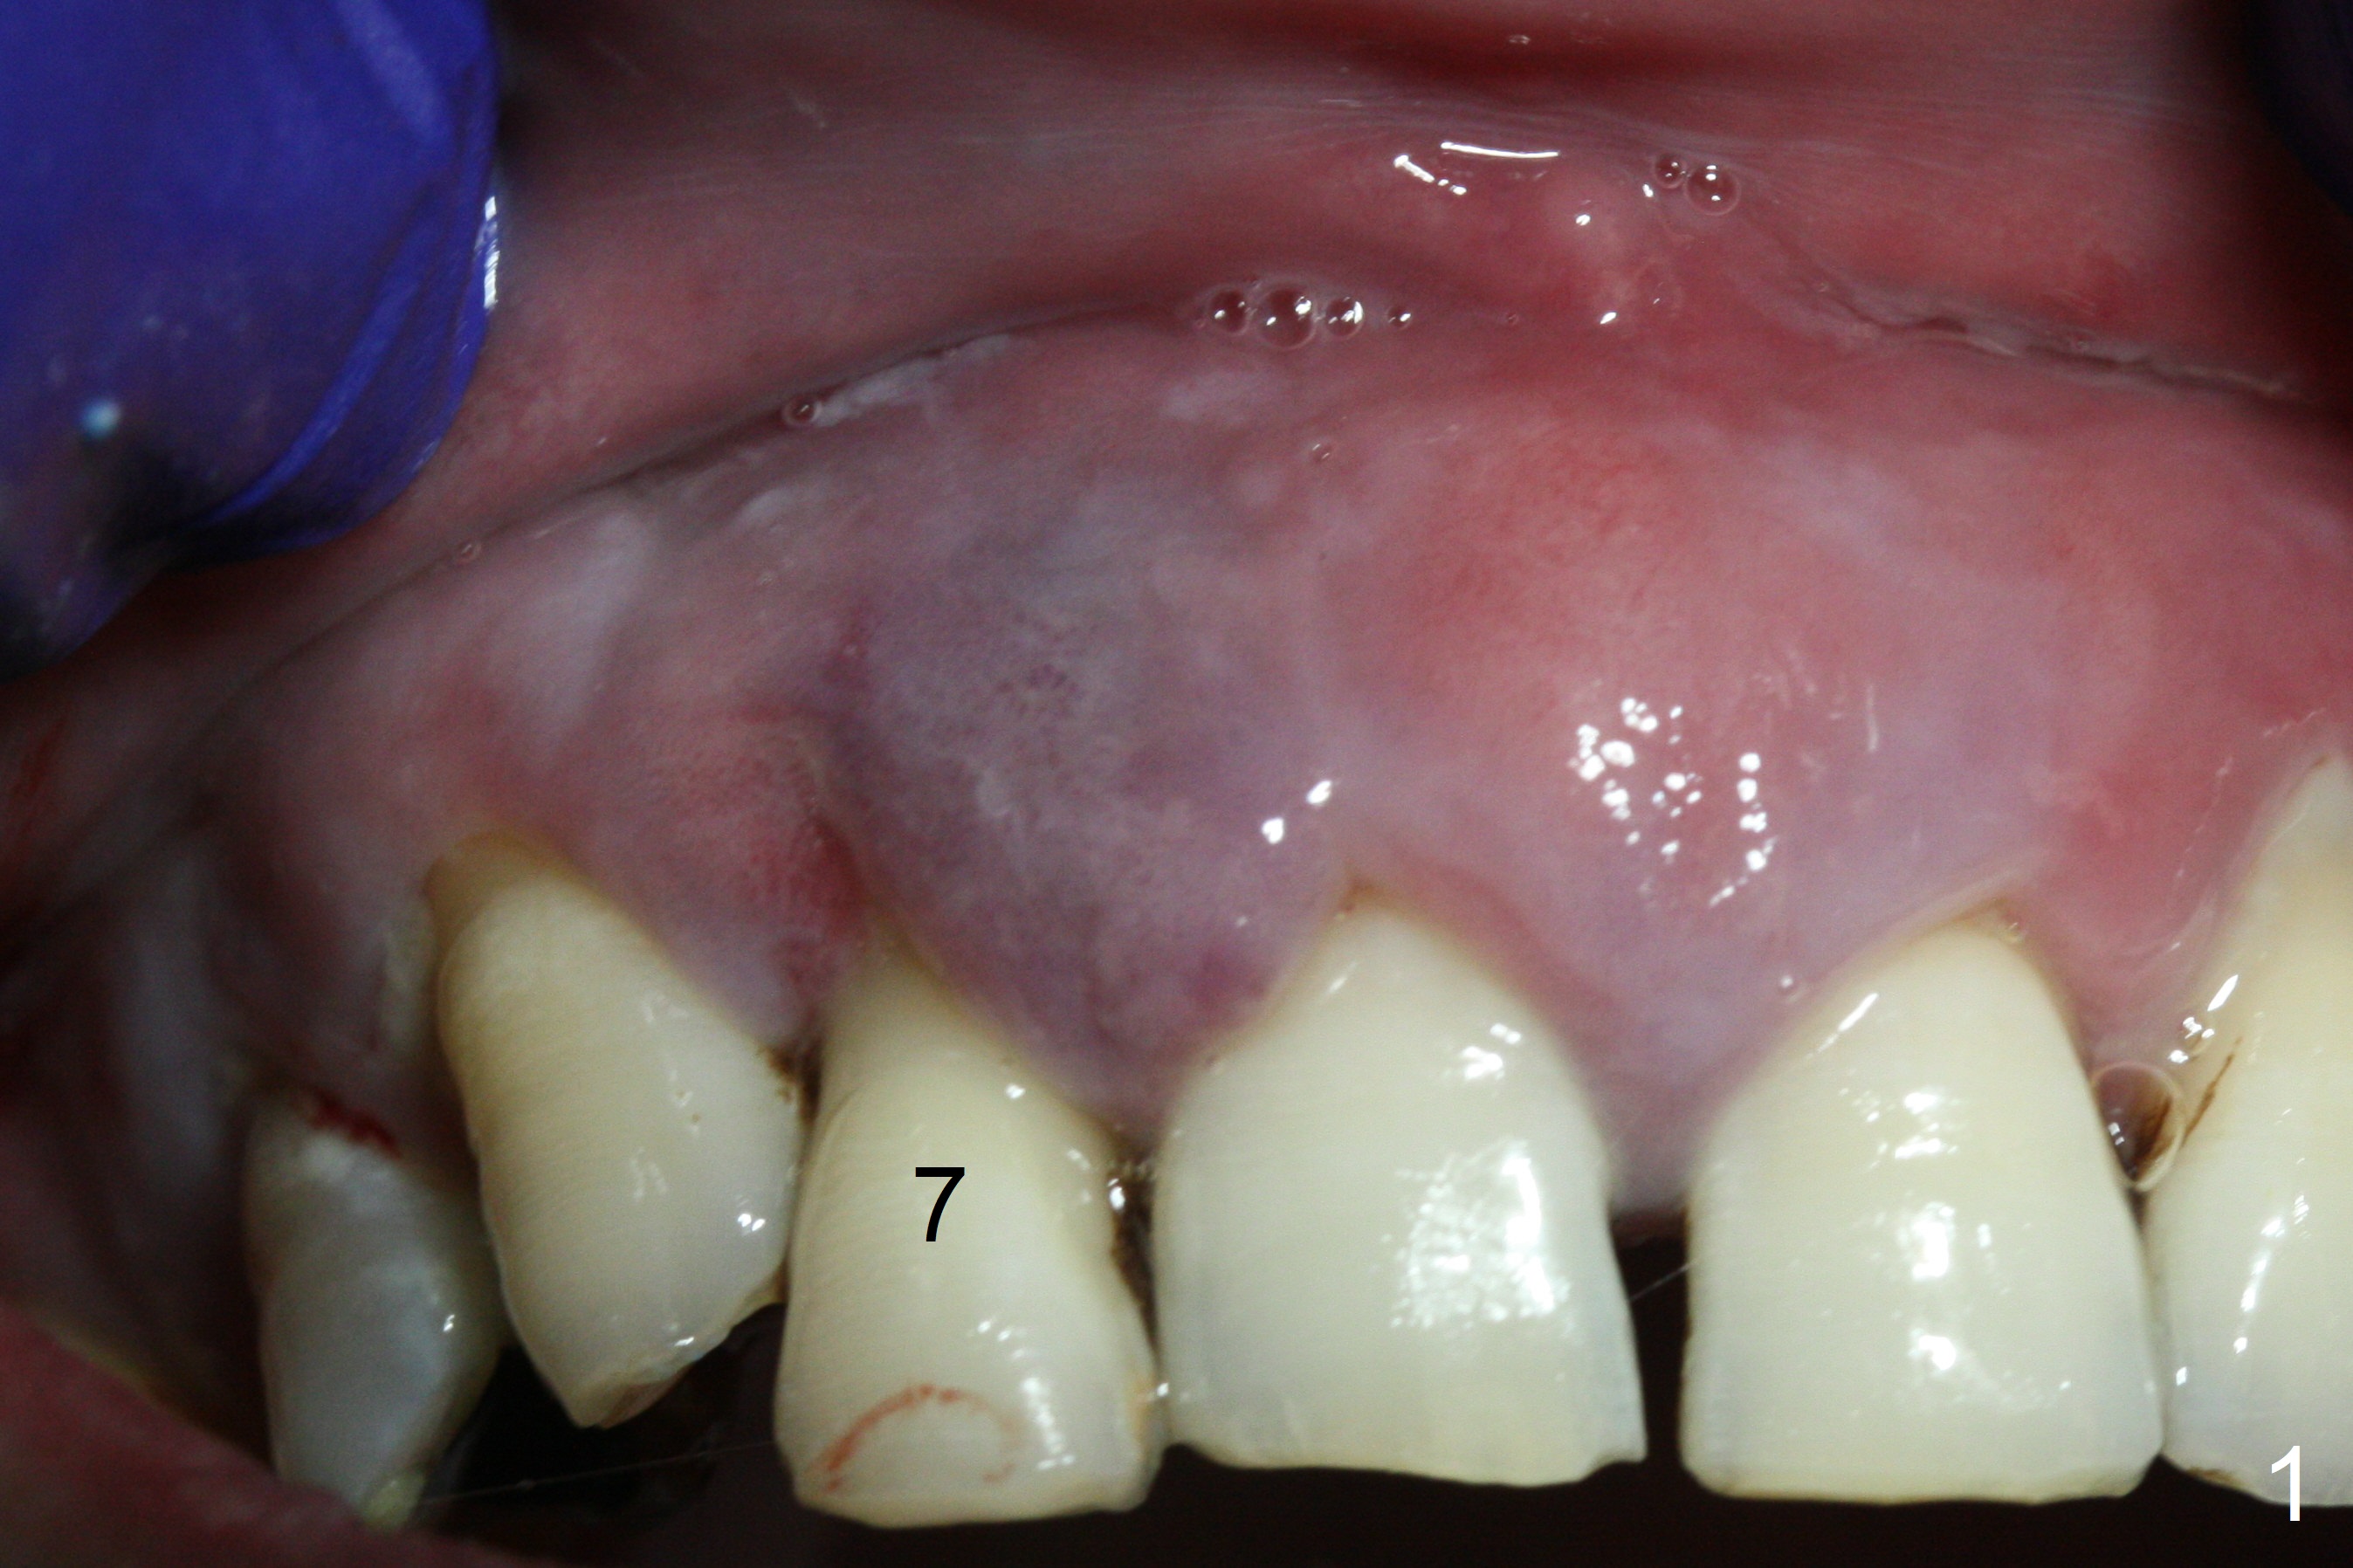

The 36-year-old man (ex-smoker, quit for 4-5 years) insists upon #3 and 5 extraction first for implants, in spite of more severe infection at #7, 14,19,30 (Fig.1-4). The gingiva around #23-26 implants is healthy 3 weeks postop (Fig.5). The initial depths at #3 and 5 are 8.5 mm (bone-level) and 18 mmm (gingiva-level (13 mm (implant length) + 5 mm cuff), respectively. When a drill penetrates the sinus floor, confirm the depth. After use of 3.8 mm drill, 4.5 mm tap drill is inserted at #3 without stability, while a 4.5x13 mm implant is placed at #5 with primary stability (Fig.6,7). Then a 5x11.5 mm is placed at #3 subcrestal proximally after sinus lift with Vanilla graft (without sinus membrane perforation; Fig.8). The implant at #5 is seated ~1 mm deeper (subcrestal mesially (^^); supracrestal distally (^)); allograft is placed around the implants prior to insertion of 6.5x7(5) and 5.5x4(5) mm abutments; last more allograft is added (Fig.9 *, 10). The implants seem to have been osteointegrated 4.5 months postop (Fig.11,12). The gingiva is healthy around the implants without bone loss 3 months post cementation (Fig.13,14).